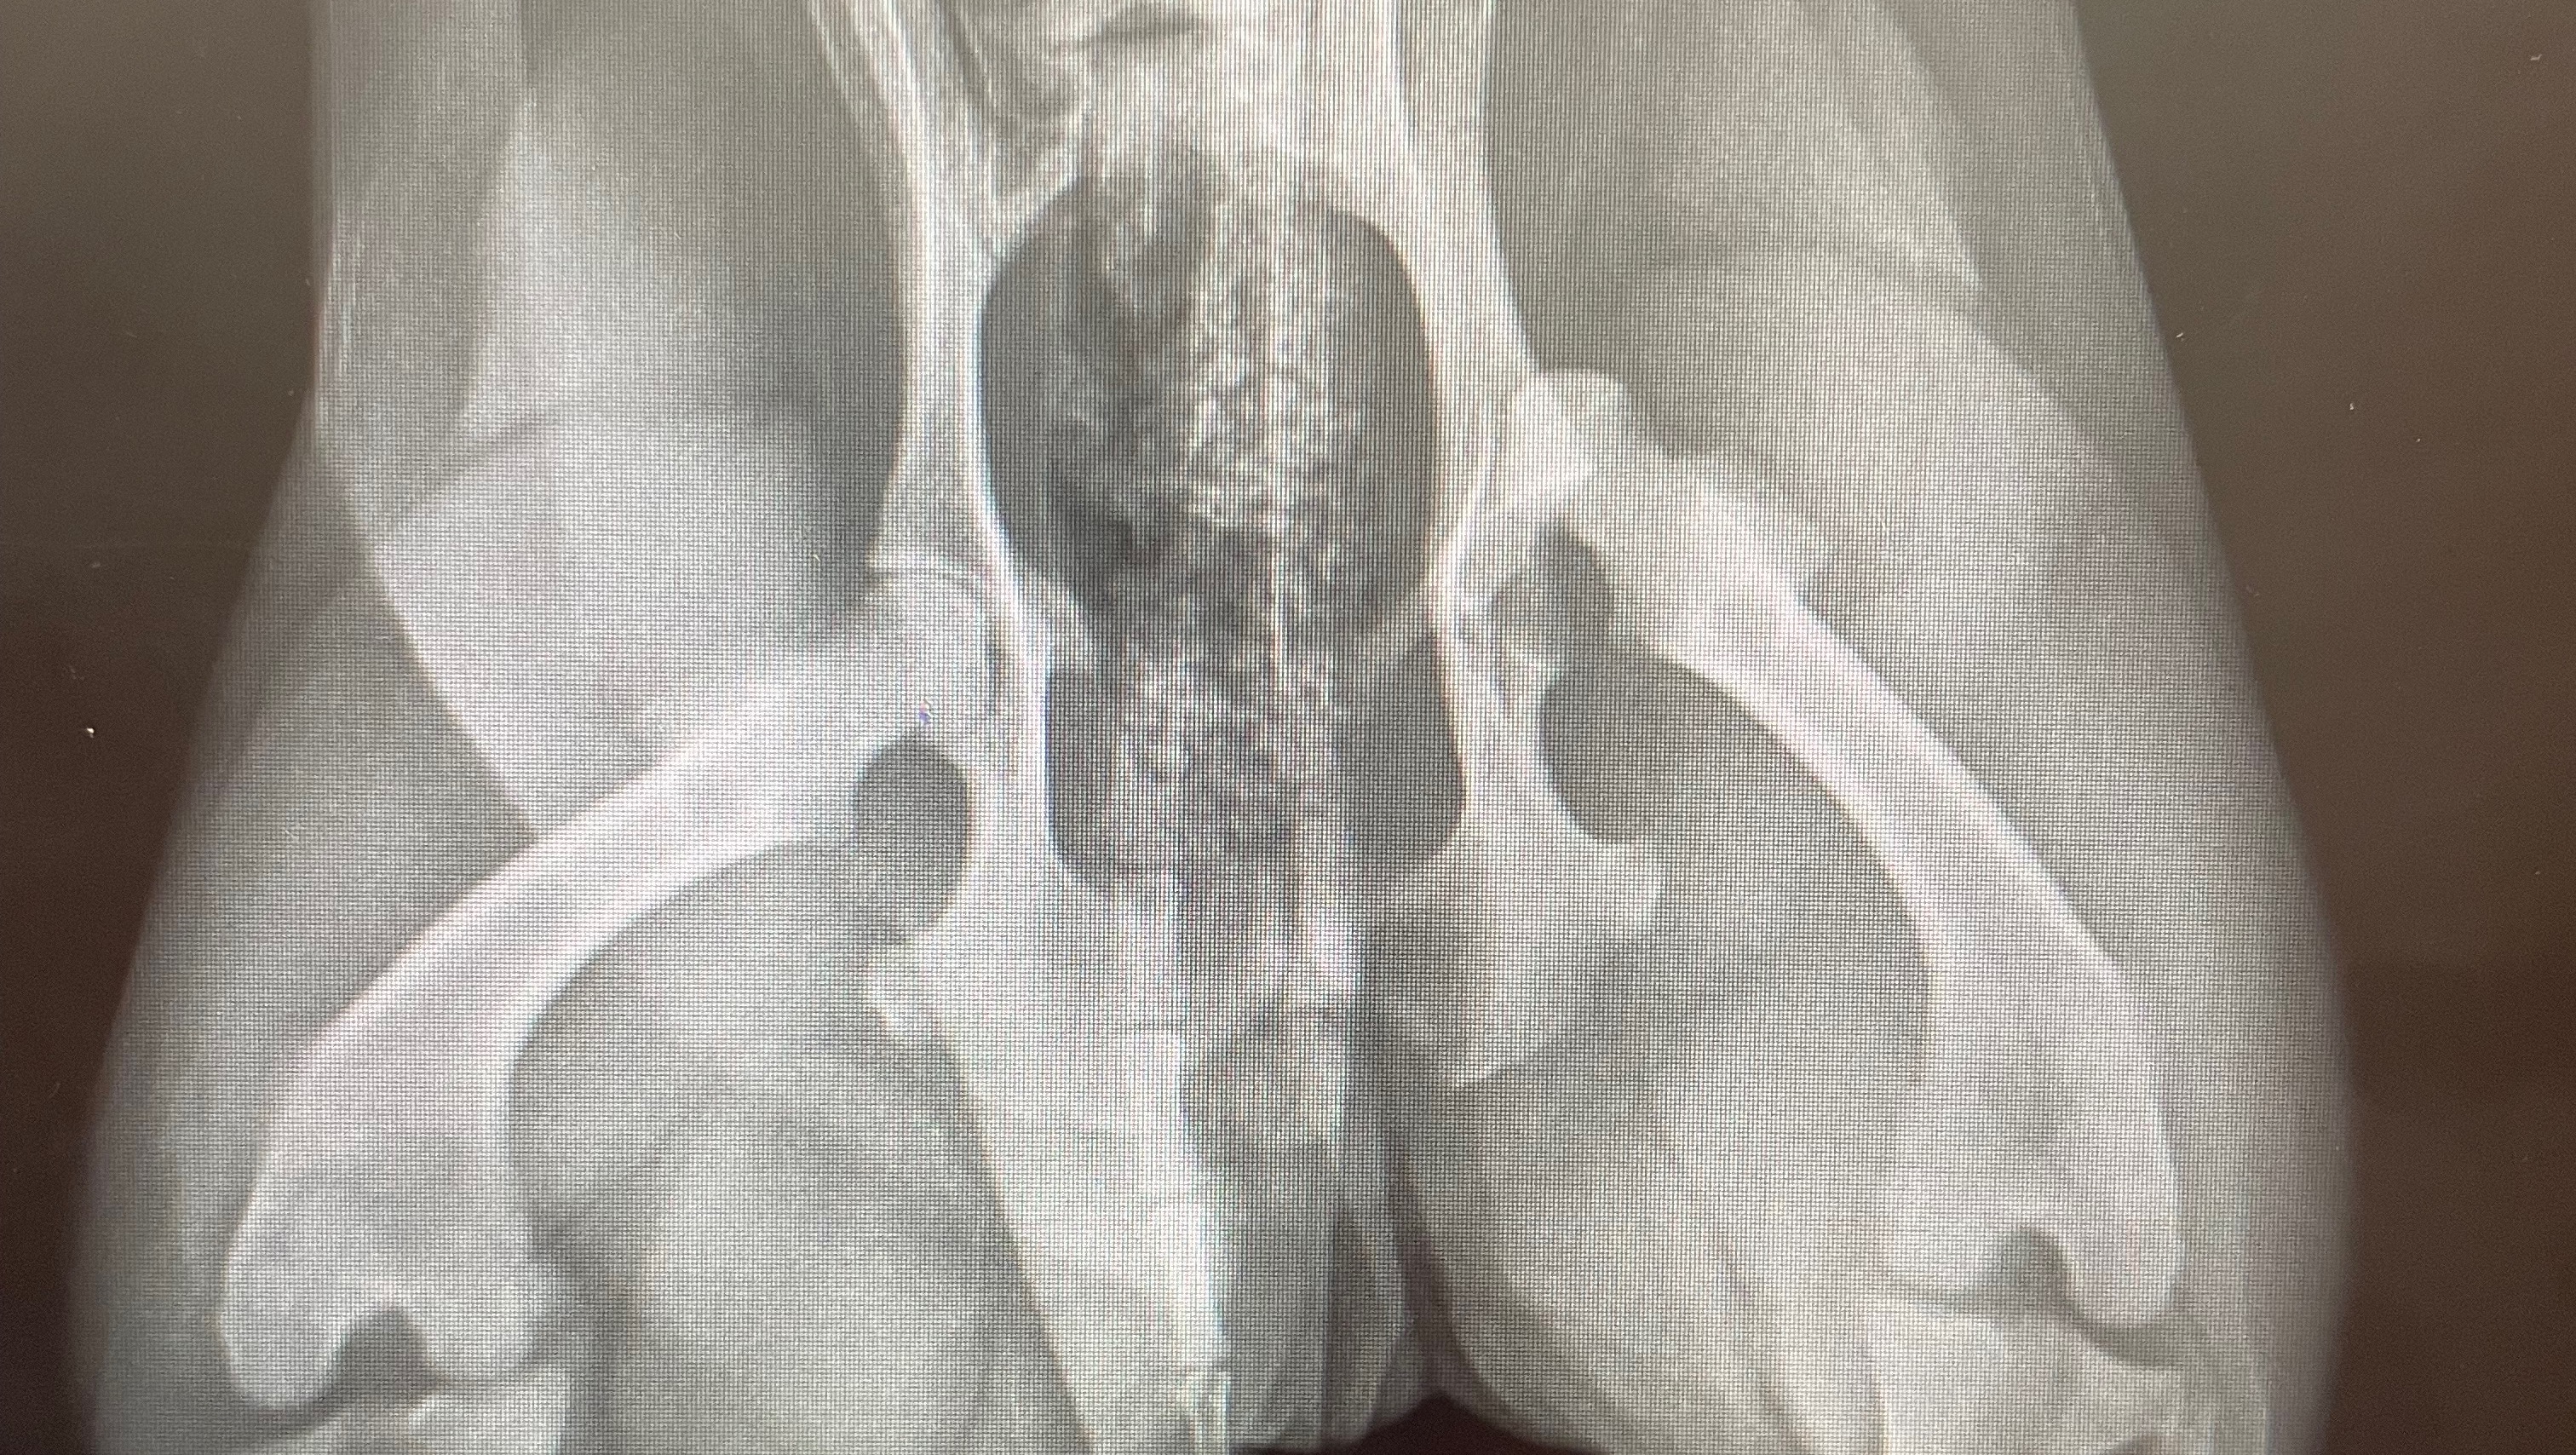

Hi, my name is Cydney Melton & my two dear friends’ dog Rascal got hit by a car July 20. Unfortunately with a dislocated back leg and a broken front leg, the surgeries will come out to $12,000. They would really appreciate the support to help pay these surgery bills, as it is a financial hardship on them and they need to help Rascal recover and get his surgeries. We would all really appreciate the help. Thank you.